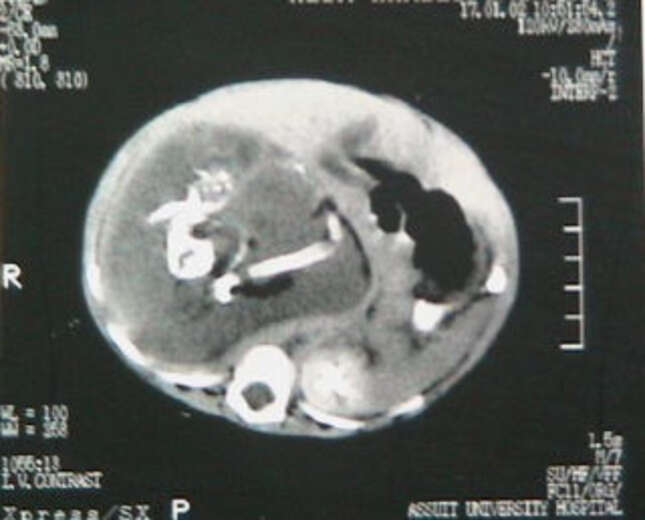

Una tomografía computarizada (CECT) con contraste abdominal mostró una masa bien definida que medía aproximadamente 25 por 23 por 15 centímetros, que se extiende desde el epigastrio [justo por encima del estómago] hasta la pelvis superior.

Mostraba áreas de densidad de grasa, tejido blando y múltiples componentes de densidad calcificada de varios tamaños y formas que se asemejan a la forma de vértebras, costillas y huesos largos. Esta masa estaba causando el desplazamiento y la compresión de las vísceras abdominales adyacentes.